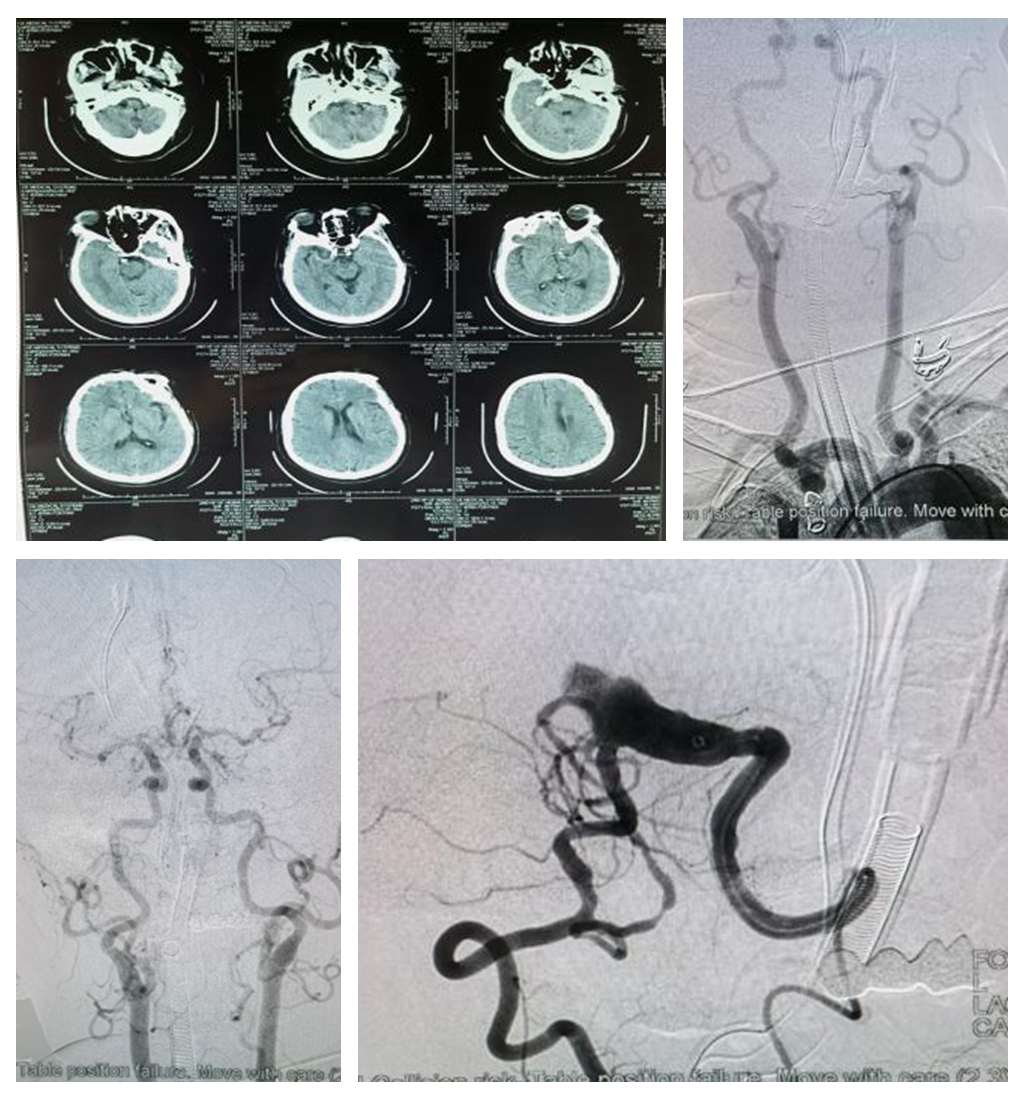

超选左锥动脉造影显示患者病变为椎-基底冗长扩张伴急性闭塞

据赵林介绍,患者为57岁女性,2月23日因突发头晕伴进展性意识不清18小时到我院急诊科救治。患者既往高血压病史10余年,口服药物控制,具体不详。一系列检查结果显示:患者是VBD基础上并发的血管急性闭塞,进而引起严重的缺血性卒中,如不及时救治,死亡率极高。

术后第三天患者意识完全清楚,双上肢肌力四级,双下肢肌力三级

为及时抢救患者,神经外科神经介入亚专业主任赵林带领董鹏飞、李京臣医生迅速对患者进行术前精准评估。患者术前检查无明显禁忌症,符合介入手术指征。签订患者家属签署知情同意书后,神外介入团队联合麻醉科徐雪主任医师,在护士刘军敏配合下在最短时间内对患者进行治疗,术中发现患者血管条件极差,使用同轴技术将中间导管顺利输送到位,并顺利使用颅内支架打通闭塞血管,患者术后第三天意识完全清楚,四肢肌力得到明显恢复。